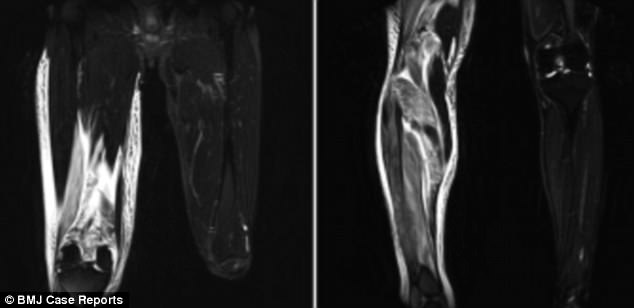

Слева и справа: показать избыток жидкости в артерии, снабжающей кровью правую ногу второго пациента

Укус вызвал паралич, который длилось два года

В июле 2008 года 42-летний мужчина, не названный по имени, обратился в больницу с жалобами на сильную боль и опухоль в ногах.

Восемнадцатью часами ранее он споткнулся в уличной канаве, и его лечили антибиотиками в другом медицинском центре.

Там его направили к специалисту после того, как врачи заподозрили, что его мягкие ткани начали умирать из-за попадания бактерий в его тело.

В специализированной больнице ему поставили диагноз ОКС, и в течение двух часов ему сделали операцию по снятию давления на ноги.

Пациент выписан на 48-е сутки с легким параличом, который полностью не исчез в течение двух лет.

«Хотя у меня были легкие симптомы паралича малоберцового нерва в течение примерно двух лет после лечения, я все еще мог выполнять свои повседневные дела».